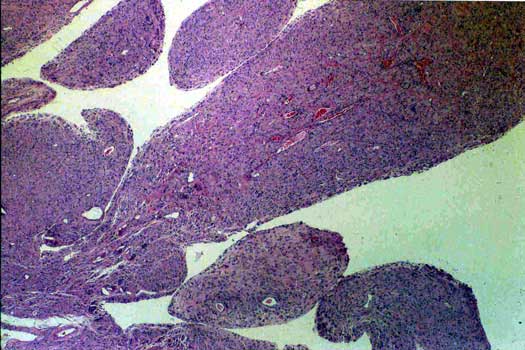

Prosthetic synovitis, low power. Hyperplastic synovial membrane obtained adjacent to prosthesis.

OSTEOLYSIS low power. Polyethylene flakes (shiny globular material) surrounded by foreign body giant cell reaction and histiocytes.